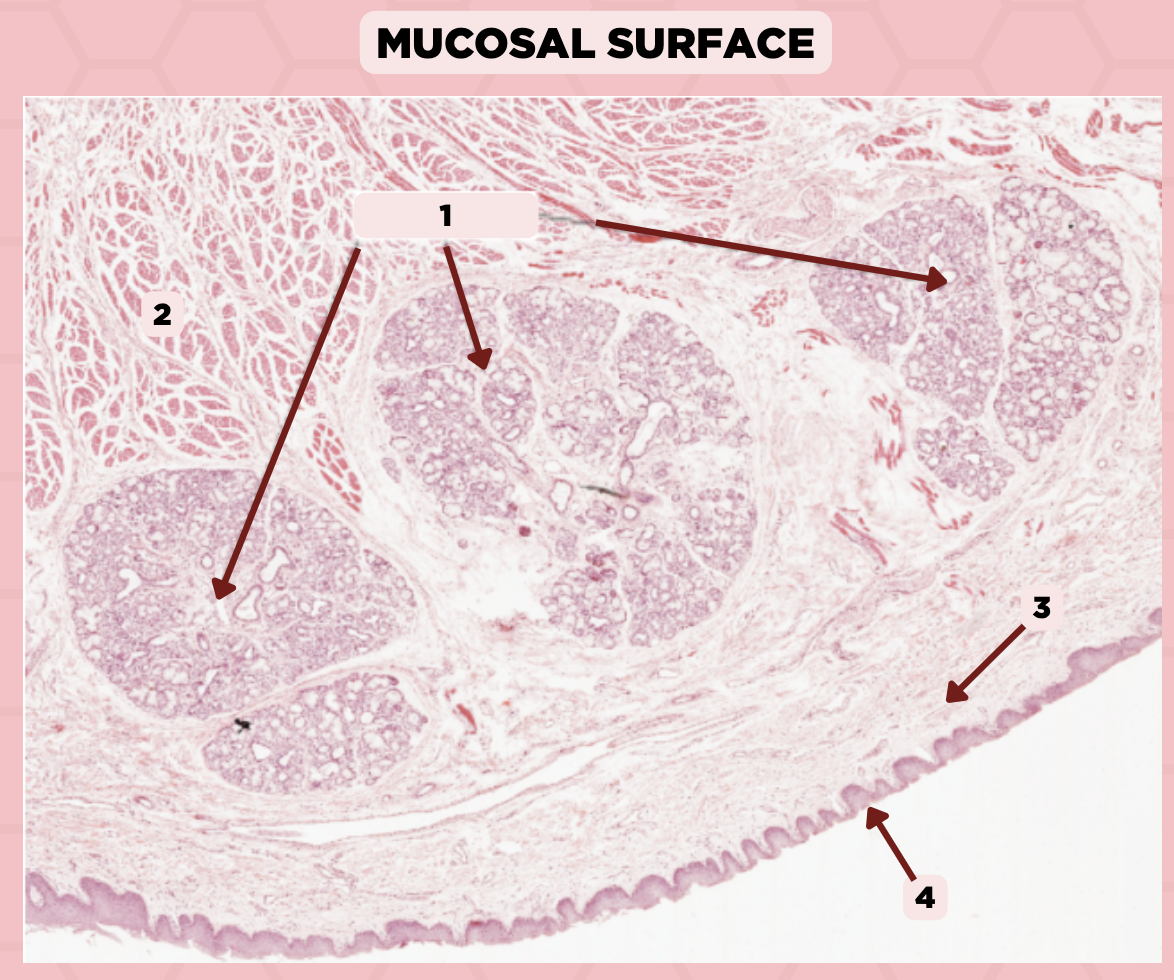

Lip

What specimen is showed in the picture?

Labial Glands (in the Mucosa)

Identify the structure labeled as 1.

Skeletal Muscle Cells

Identify the structure labeled as 2.

Lamina Propria

Identify the structure labeled as 3.

Mucosa

Identify the structure labeled as 4.

Lip

What specimen is showed in the picture?

Skeletal Muscle Fibers

Identify the structure labeled as 1.

Labial Glands

Identify the structure labeled as 2.